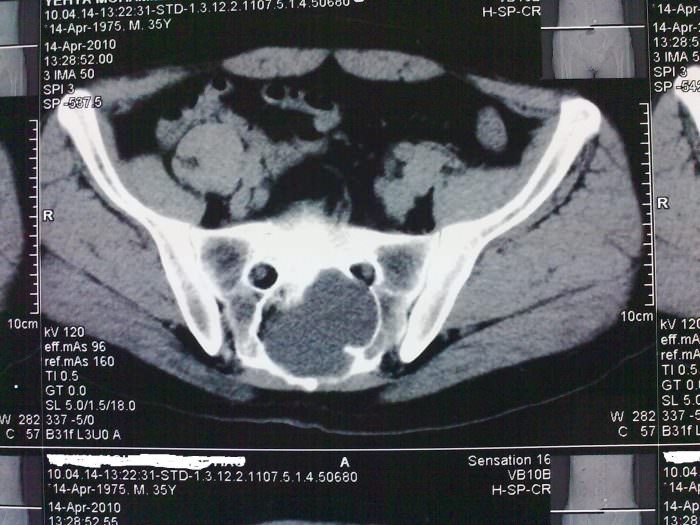

КТ малого таза – процедура сканирования внутренних органов для дальнейшей диагностики. Это точная процедура, помогающая информативно изучить органы малого таза.

Что показывает процедура? Компьютерная томография дает информацию о следующем:

- Есть ли воспаление органов.

- Наличие или отсутствие новообразований, а также опухолей (раковых и доброкачественных).

- Мочевой пузырь и его состояние.

- Последствия травм и ушибов в области таза.

КТ имеет такие же плюсы, как и МРТ, но назначается в случае невозможности провести магнитно-резонансную томографию. МРТ помогает лучше рассмотреть ткани внутренних органов, но не дает информации о костях. Поэтому для изучения мышц и остальных тканей лучше, по возможности, использовать магнитно-резонансную томографию, а если нужна информация более обширного характера – компьютерная томография.

КТ органов малого таза позволяет выявить и дифференцировать все объемные образования (кисты, опухоли, абсцессы), определить выраженность и распространенность воспалительного процесса, наличие жидкости, крови, гноя в малом тазу, определить характер врожденных аномалий, особенности строения органов, их размер и